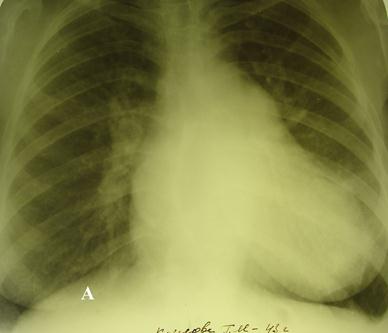

При обследовании можно наблюдать усиленный верхушечный толчок, который смещен влево и вниз. Аускультативно отмечается ослабление, а иногда и полное отсутствие первого тона. Это объясняется тем, что нет периода замкнутых клапанов. Таким образом, отсутствует клапанный компонент происхождения первого тона. Выслушивается акцент второго тона над лёгочной артерией. Он обусловлен гипертензией в лёгочной артерии. Наиболее характерным симптомом митральной недостаточности является систолический шум, который лучше выслушивается над верхушкой сердца или в точке Боткина. Шум обусловлен обратной волной крови (регургитацией) в левое предсердие между неплотно сомкнутыми митральными створками во время систолы левого желудочка. Тембр шума может быть мягким, дующим или грубым. При рентгеновском обследовании в прямой проекции отмечается значительное, преимущественно левостороннее, расширение размеров сердца. Имеет место закругление четвертой дуги на левом контуре сердца. Это является отражением увеличения и гипертрофии левого желудочка. Также имеется выбухание третьей дуги левого контура за счет увеличения левого предсердия, что обуславливает сглаживание талии сердца (рис. 100).

Рис. 100. Рентгенограмма больной К. с комбинированным митральным пороком сердца с преобладанием недостаточности. Легочная гипертензия. А.- Прямая проекция. Усиленный легочной рисунок. По левому контуру сердца увеличение 2 и 3 дуг. Увеличение левого желудочка (4 дуга). На правом контуре сердца дополнительная дуга, создающая симптом перекрестка – обусловлена перерастяжением резко увеличенного левого предсердия, который выходит на правую сторону сердца.